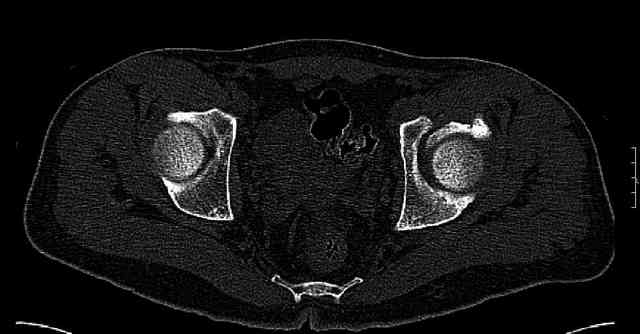

Re: Нелеченный перелом вертлужной впадины

Some more images. Does it help to guess which part of the acetabulum is displaced?